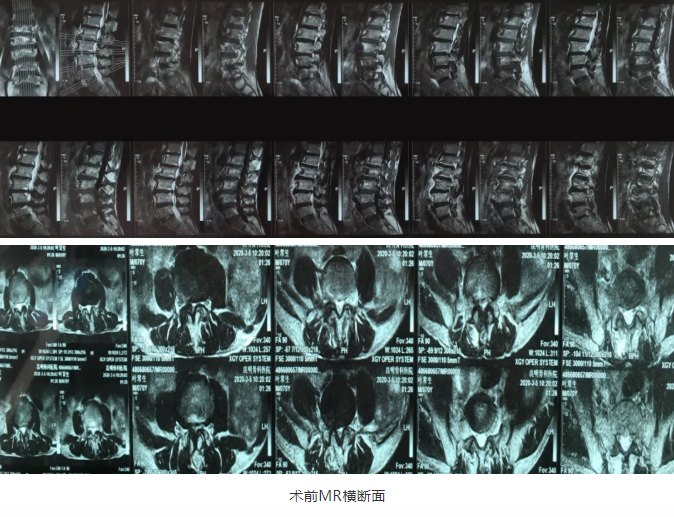

“OLIF作为一种更加微创的椎间融合术,近几年在国内各大医院逐渐开展,获得越来越多临床医生的认可”桃春辉院长介绍,该手术经左下腹腹外斜肌、腹内斜肌、腹横肌的肌间隙进入腹膜外间隙,在左侧腰大肌和腹主动脉之间安放工作通道,可通过大血管间隙及腰大肌间入路进行手术,可明显减少手术创伤、缩短手术时间、减少术中出血、缩短住院时间及患者康复时间。